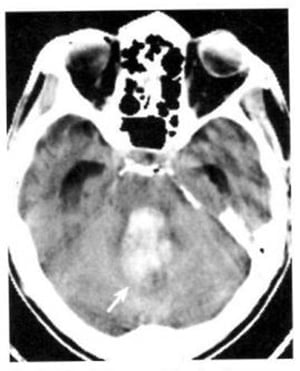

2.2. Xuất huyết (Hình 1.68)

Dấu hiệu XQCTĐT:

– Tổn thương mật độ cao gây chèn ép hoặc tắc nghẽn não thất 4 dẫn tới não úng thủy.

Chú giải:

– Xuất huyết vào trong bể có thể xuất hiện như những lớp mật độ cao nằm kế cận lều tiểu não hoặc các bể.

Hình 1.68. Xuất huyết trong não thất. Não thất 4 chứa máu, giãn nở và có mật độ cao (mũi tên). Các sừng thái dương giãn nở chứng tỏ có tắc nghẽn.